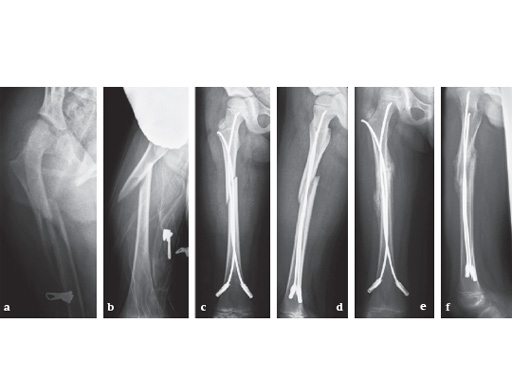

6-year-old girl, ski injury.

ab

X-rays show a long spiral fracture of the proximal third of the right femur (32D/5.1). Because of the age good indication for ESIN, but some danger of instability is possible.

cd

Postoperative x-rays. A closed reduction and fixation with 3.0 mm TEN was carried out with correct child-oriented alignment. For stability reasons two End Caps became uses. No signs of a shortening can be seen.

ef

AP and lateral view 6 weeks after surgery shows good callus formation and still a perfect alignment.

Full weight bearing was then allowed.